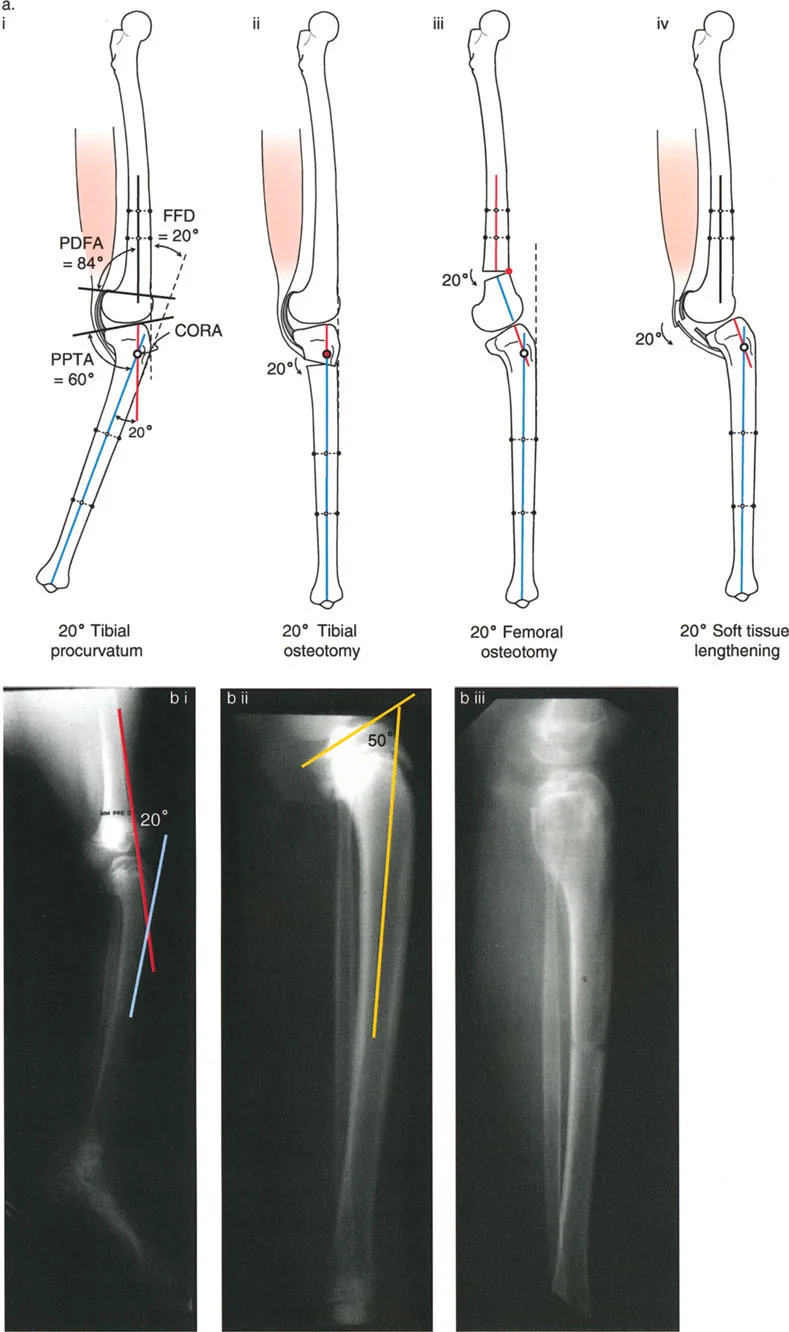

تصحيح تحدد حركة الركبة (Flexion Deformity - FFD)

تحدُّد حركة الركبة هو عدم القدرة على مد الركبة بالكامل. يمكن أن يكون سببه عظميًا أو ناتجًا عن تقلص في الأنسجة الرخوة.

- التشخيص الدقيق: يجب تحديد ما إذا كان تحدد الحركة ناتجًا عن تشوه عظمي (تقوس أمامي في الفخذ أو الساق) أو تقلص في الأنسجة الرخوة (الأوتار الخلفية، محفظة المفصل).

- قطع العظم التمديدي (Extension Osteotomy):

- إذا كان التشوه عظميًا، يتم إجراء قطع عظم تمديدي في عظم الفخذ أو الساق لتصحيح التقوس.

- الأستاذ الدكتور محمد هطيف يؤكد على أهمية عدم تصحيح الساق بأكثر من 90 درجة PPTA لتجنب فقدان الميل الخلفي الطبيعي للساق.

- تحرير الأنسجة الرخوة (Soft Tissue Release):

- إذا كان السبب هو تقلص الأنسجة الرخوة، فقد يتم إجراء إطالة للأوتار أو تحرير لمحفظة المفصل.

- إزالة النتوءات العظمية (Osteophyte Resection):

- إذا كانت النتوءات العظمية الأمامية تمنع المد الكامل، يمكن إزالتها جراحيًا.

- التصحيح التدريجي: في حالات تحدد الحركة الشديدة أو المعقدة، قد يكون التصحيح التدريجي باستخدام التثبيت الخارجي هو الخيار الأكثر أمانًا.

تصحيح الركبة الارتدادية (Recurvatum Deformity - Hyperextension)

الركبة الارتدادية هي فرط البسط في الركبة. غالبًا ما تكون غير مصحوبة بأعراض في الأشخاص ذوي العضلات السليمة، ولكنها قد تسبب مشاكل في حالات ضعف العضلات أو التشوهات العظمية.

- التشخيص: يجب تحديد ما إذا كانت الارتدادية عظمية (تقوس خلفي في الفخذ أو الساق) أو ناتجة عن رخاوة في الأنسجة الرخوة أو ضعف عضلي.

- قطع العظم الانثنائي (Flexion Osteotomy):

- إذا كان التشوه عظميًا (تقوس خلفي)، يتم إجراء قطع عظم انثنائي في عظم الفخذ أو الساق لتصحيح الارتدادية.

- الأستاذ الدكتور محمد هطيف يشدد على أهمية عدم استخدام قطع عظم الفخذ الانثنائي لتصحيح ارتدادية الساق، والعكس صحيح، لتجنب الانزلاق الخلفي أو الأمامي للركبة.

- اعتبارات خاصة: في المرضى الذين يعانون من ضعف عضلي (مثل شلل الأطفال)، قد يحتاج التصحيح إلى فرط تصحيح بسيط (overcorrection) إلى وضعية انثناء لضمان ثبات الركبة ومنع فرط البسط غير المتحكم فيه.